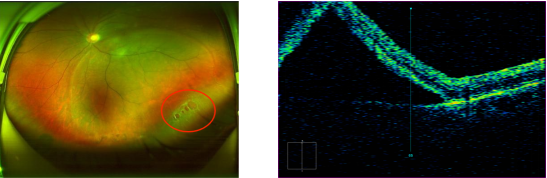

△术前(第一、二幅图)、术后七天(第三、四幅图)的左眼欧堡眼底和黄斑OCT对比图